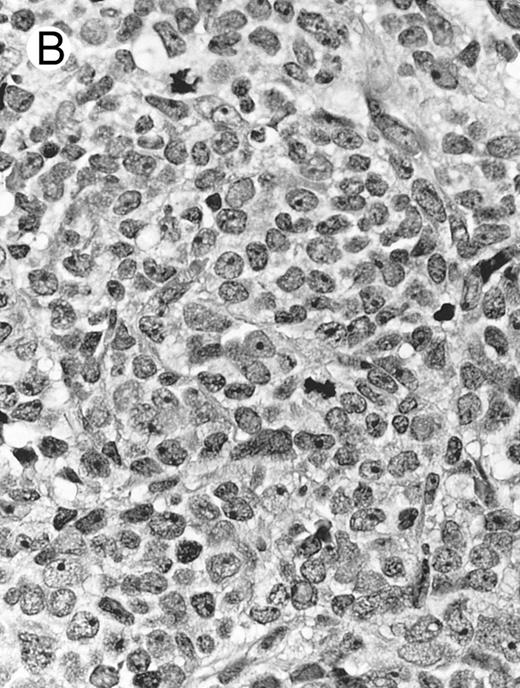

Blastoid NK cell lymphoma (case no. 40). (A) Biopsy shows a diffuse lymphomatous infiltrate with a prominent single-file pattern. (B) The neoplastic cells are medium-sized and possess fine chromatin. Mitotic figures are seen. There is remarkable resemblance to myeloid leukemic infiltration.

Blastoid NK cell lymphoma (n = 2).One patient presented with systemic disease, whereas 1 had localized disease at presentation. Histologically, the infiltrate was diffuse, with a prominent single-file pattern reminiscent of leukemia (Fig 8A). The neoplastic cells were medium-sized and had irregularly folded delicate nuclear membranes, fine chromatin, and tiny nucleoli (Fig 8B). Mitotic figures were easily identified.